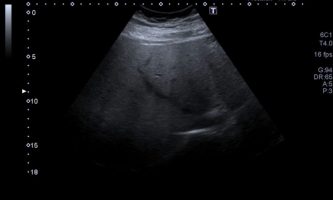

El médico de referencia le indica nueva ecografía de control, donde se observan múltiples y extensas lesiones focales hepáticas hiperecogénicas, redondeadas y confluentes, las cuales predominan en adyacencia a venas supra hepáticas, sin condicionar efecto de masa y sin alteración de la superficie hepática(fig. 1 y 2). Ante la valoración con Doppler color no presenta patrón de flujo peri ni intralesional y respeta el calibre de las venas supra hepáticas(fig. 3 y 4). Dada las características ecográficas se sospecha esteatosis focal multinodular confluente como principal diagnóstico presuntivo, siendo los diagnósticos diferenciales patologías de naturaleza infecciosa, tumoral o metastásica.

El examen radiológico abdominal más comúnmente utilizado en prevención es la ecografía (US) dado que es un método económico y accesible, no invasivo y que no utiliza rayos X, con el cual se logra fácilmente el diagnóstico de esteatosis, dado que se reconoce aumento difuso de ecogenicidad del parénquima hepático. Los criterios principales: la ecogenicidad del parénquima hepático debe ser mayor que la de la corteza renal, mala definición diafragmática, de los vasos supra hepáticos y de la arquitectura intra hepática.2(fig. 8, 9a y 9b)